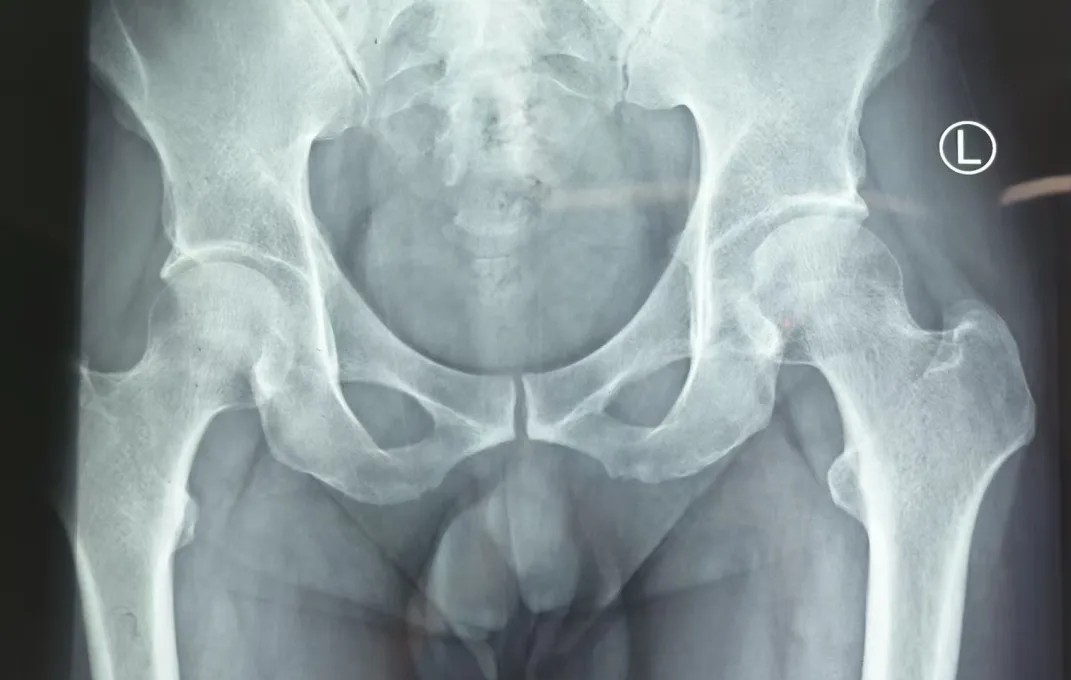

股骨頭壞死早期症狀不典型,很(hěn)容易咊(he) “腰腿痛”“關節(jie)炎” 混淆,加(jia)上一(yi)般的(de)X線(xiàn)檢(jian)查不易髮(fa)現(xian)早期的(de)股骨頭壞死,許多(duo)患者因此耽誤治療。當身體(ti)出現(xian)以(yi)下表現(xian)時,不要忽視:

對于(yu)股骨頭壞死的(de)治療。核心目(mu)标昰(shi)保護股骨頭的(de)完整性,盡量延緩或避免關節(jie)置換手術(shù)。根據病情、股骨頭塌陷程(cheng)度以(yi)及(ji)患者自身情況,需要選擇适郃(he)患者的(de)治療方(fang)案。